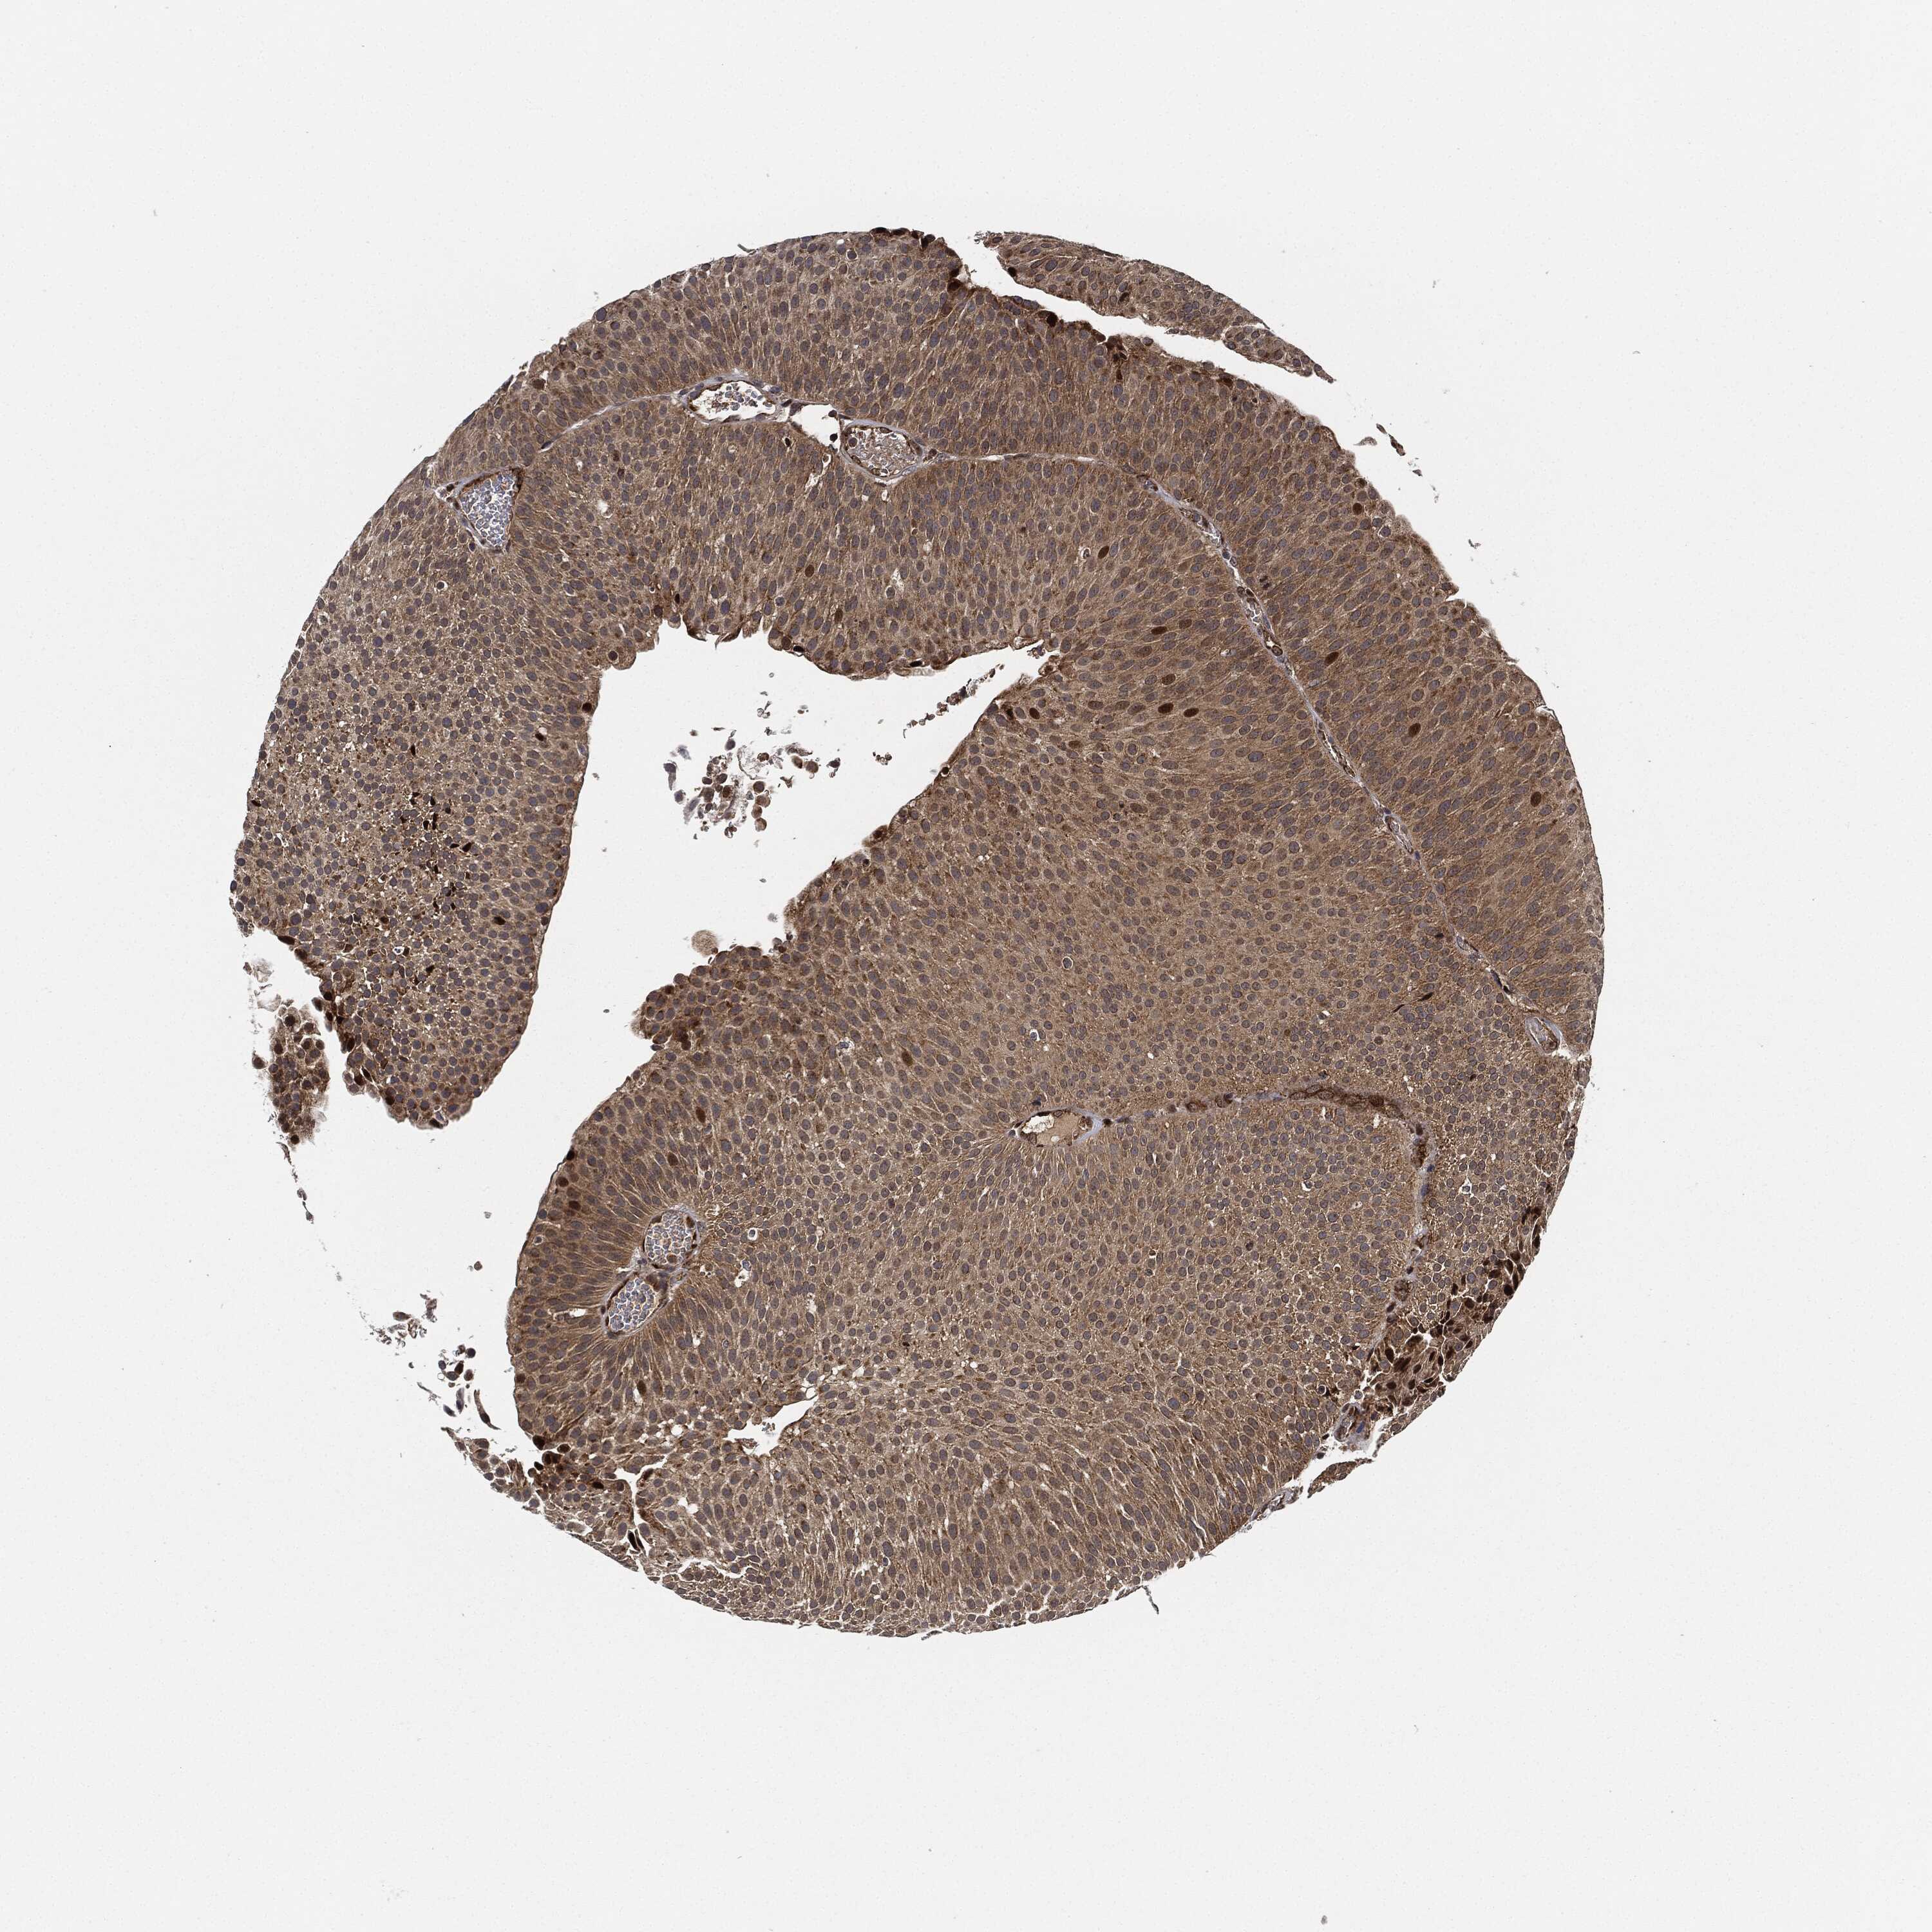

UROTHELIAL CANCER - Protein expressioni

A mouse-over function shows sample information and annotation data. Click on an image to view it in a full screen mode. Samples can be filtered based on level of antibody staining by selecting one or several of the following categories: high, medium, low and not detected. The assay and annotation is described here.

Antibody stainingi

Antibody staining in the annotated cell types in the current human tissue is reported as not detected, low, medium, or high, based on conventional immunohistochemistry profiling in selected tissues. This score is based on the combination of the staining intensity and fraction of stained cells.

Each image is clickable and will lead to virtual microscopy that enables deeper exploration of all samples and also displays staining intensity scores, fraction scores and subcellular localization as well as patient and tissue information for each sample.

Antibody HPA002633

Antibody HPA046758

Antibody CAB010906

Staining

High

Medium

Low

Not detected

Intensity

Strong

Moderate

Weak

Negative

Quantity

>75%

75%-25%

<25%

None

Location

Nuclear

Cytoplasmic/membranous

Cytoplasmic/membranous,nuclear

Urothelial carcinoma, High grade

Urothelial carcinoma, Low grade